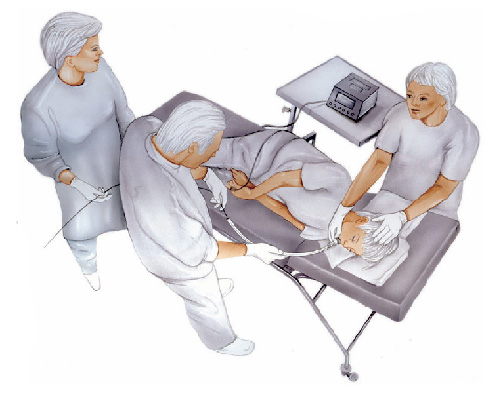

Realizado introduzindo-se pela boca um aparelho flexível com iluminação central que permite a visualização de todo o trajeto examinado.

O exame é realizado com anestesia tópica (um spray de anestésico na garganta) e com sedação, utilizando medicação administrada por uma veia para permitir que você relaxe e adormeça.

O que acontecerá durante o exame ?

Você não sentirá dor, as vezes apenas um leve desconforto na garganta durante a passagem do aparelho e no estômago durante a insuflação do órgão com ar.

A medicação sedativa pode ainda causar sensação de ardência no local da infusão e no trajeto da veia puncionada (flebite).

Caso não haja intercorrências, a duração média do procedimento é de 10 minutos.